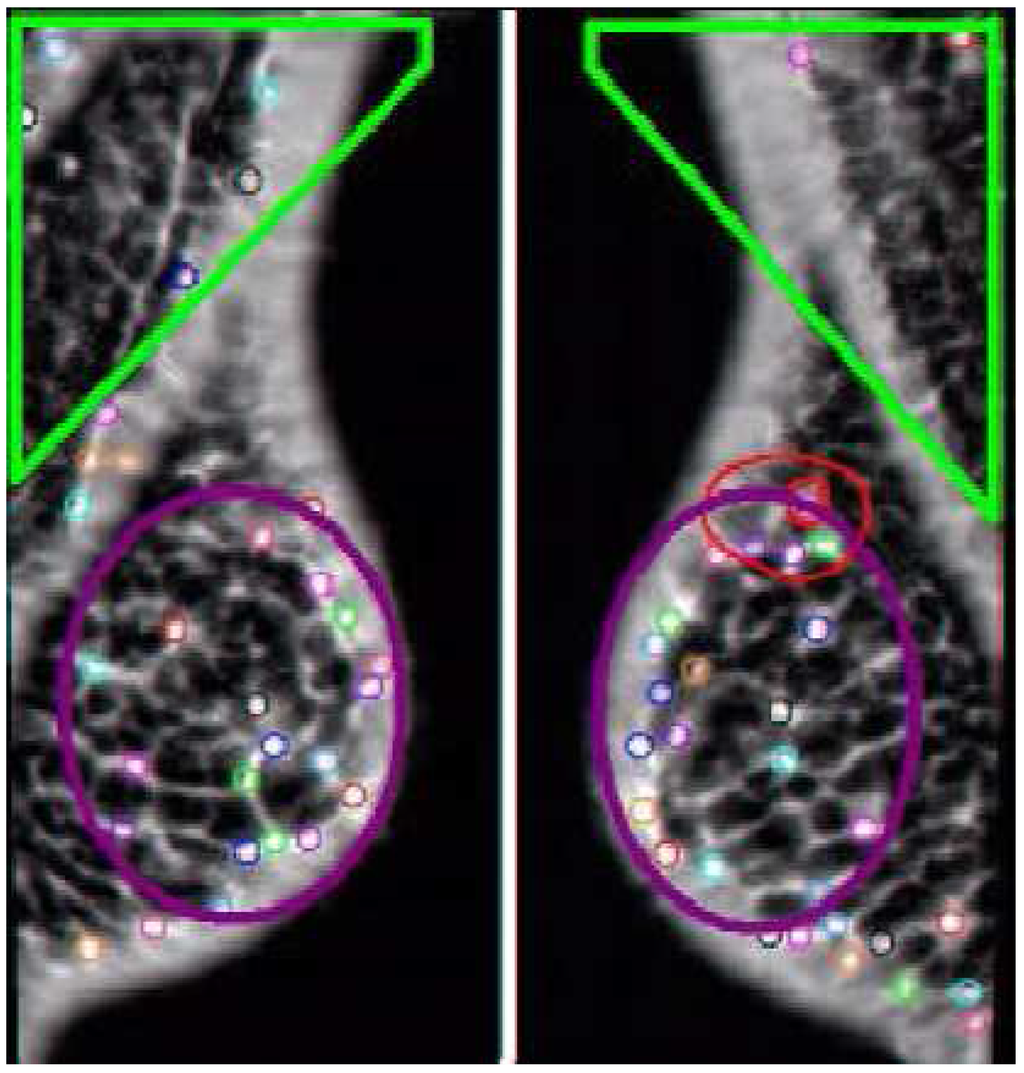

Figure 4. The distribution of the AFUM features on a mammogram are shown as small circles, while the larger oval shapes are hand-drawn annotations by a radiologist of the cancer. Note that the feature does find a cancer, but there are many false positives.